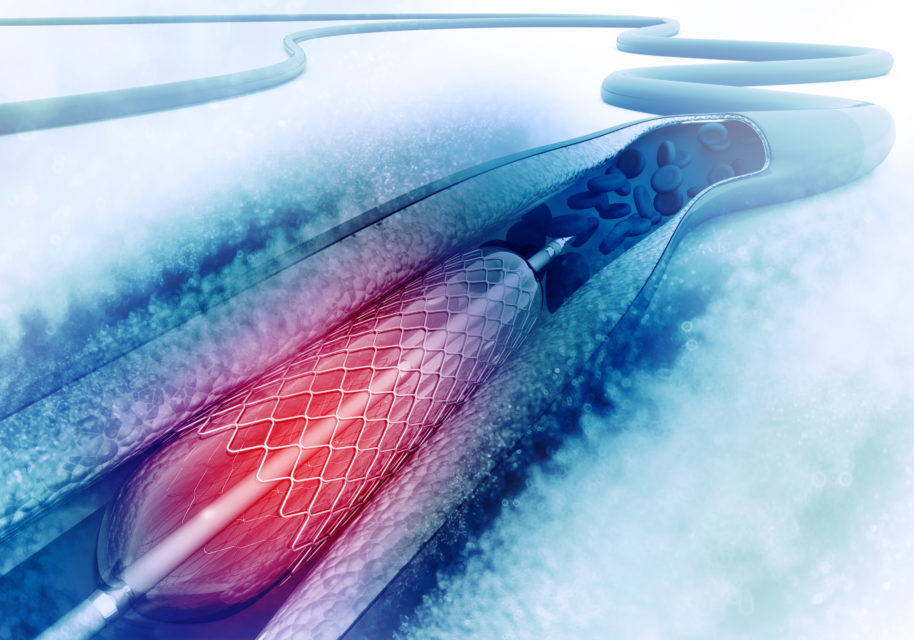

In the BASKET-SMALL 2 randomized controlled trial, researchers compared the effect of a drug-coated balloon (DCB) ...

Practice Tips with Dr. Lichaa: Perforated Balloon No Reflow

A study presented at the Transcatheter Cardiovascular Therapeutics (TCT) 2021 Annual Meeting investigated long-term ...

A pooled analysis of randomized trials found that moderate to severe coronary artery calcification (CAC) is associated ...